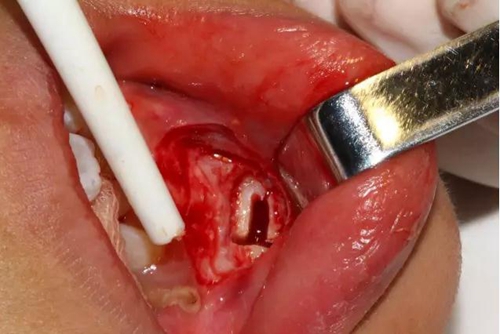

去除骨皮質(zhì),暴露牙冠大部分

設(shè)計冠切的位置

橫斷牙冠,注意深度的把控